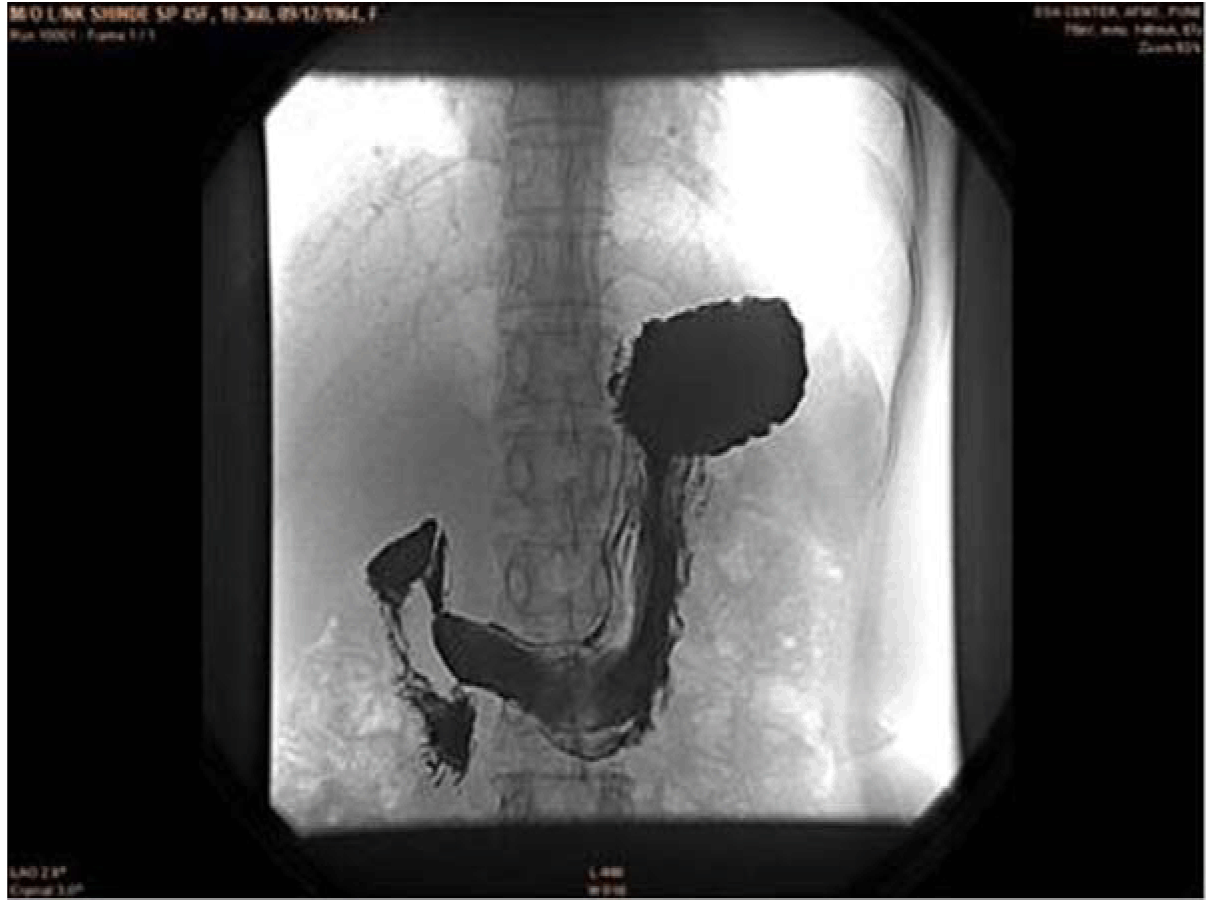

On admission to the hospital, chest and abdominal X-rays were performed which were inconclusive. Routine laboratory studies including hematological and biochemical parameters were normal. Serum amylase was within normal limits. Following this an ultrasound of the abdomen was performed. Ultrasound showed a well-delineated, multi-loculated, cystic lesion of size 5.2x6.2x7.7 cm in the body of the pancreas. The cysts were all subcentimetric giving a honeycomb appearance to the lesion. (Figure 1) Subsequently, a barium meal study was done which showed a smooth extrinsic indentation on the lesser curvature of the stomach. (Figure 2) Contrast-enhanced computed tomography scan showed a large, lobulated, well defined, lesion with multiple subcentimetric non enhancing hypodense cystic areas with enhancing hyperdense walls in the body of pancreas. (Figure 3) Multiple discrete foci of calcifications were seen within the lesion. (Figure 4) Anteriorly the lesion was reaching till anterior abdominal wall, posteriorly it was abutting the splenic vein, superiorly it was abutting the segment IV of liver and inferiorly it was abutting lesser curvature of stomach. After complete investigations, patient was diagnosed as a case of cystic tumor of pancreas and she was operated upon with resection of the lesion. Histology of resected pancreatic tissue revealed multicystic lesion in the body of pancreas containing cysts less than 1 cm in size lined by small flat to cuboidal cells. (Figure 5) There was no architectural or cytological atypia noted. Based on the imaging findings and further confirmation by histopathology a diagnosis of serous cystadenoma of pancreas was made.

Figure 2: Barium meal showing a smooth indentation on lesser curvature of the stomach.